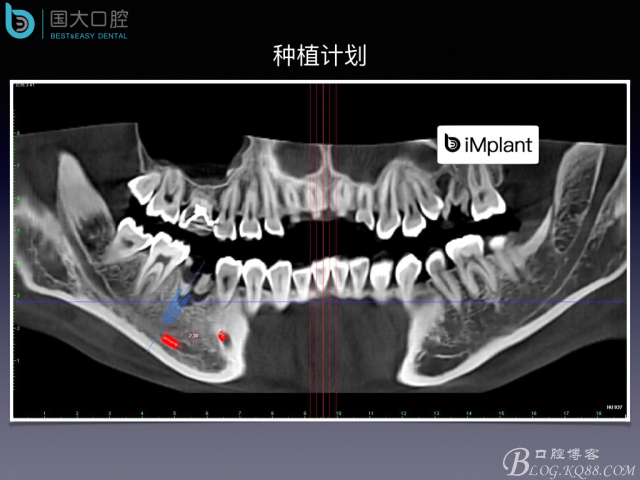

TypeC Socket即刻種植臨床案例

來源于國大口腔 邵現(xiàn)紅醫(yī)生發(fā)表的博文